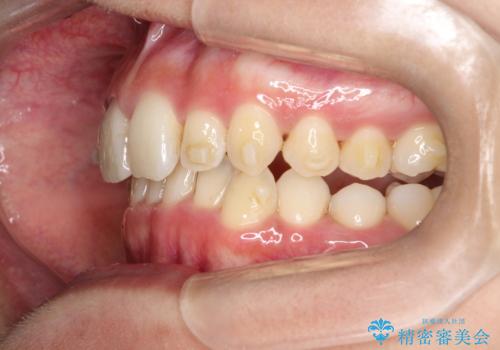

ディープバイト改善のためのインビザライン治療

- 患者様は、全体的な歯列のガタガタとディープバイト(深い噛み合わせ)を主訴として来院されました。診断の結果、ディープバイトを改善するためには、歯列全体の拡大が必要であると判断しました。治療には、透明なマウスピース型矯正装置「インビザライン」を使用し、歯を適切に拡大しながら歯並びを整える計画を立てました。治療期間はおおよそ2年を見込んで進め、最終的に見た目にも大きく変化をもたらすことを目指しました。

ディープバイトの治療には、奥歯の高さや前歯の位置に対する繊細な調整が必要です。本症例では、インビザラインによる歯列拡大を行うことで、噛み合わせを改善し、歯並び全体を整えました。治療過程では、歯間のスペースを確保するため、IPR(インタープロキシマルリダクション)を適宜行い、無理なく歯列の調整を行いました。治療後は、歯並びが大きく改善され、患者様の見た目にも大きな変化が現れました。インビザラインは透明で目立たず、治療中の見た目を気にされる患者様にも配慮した治療法です。